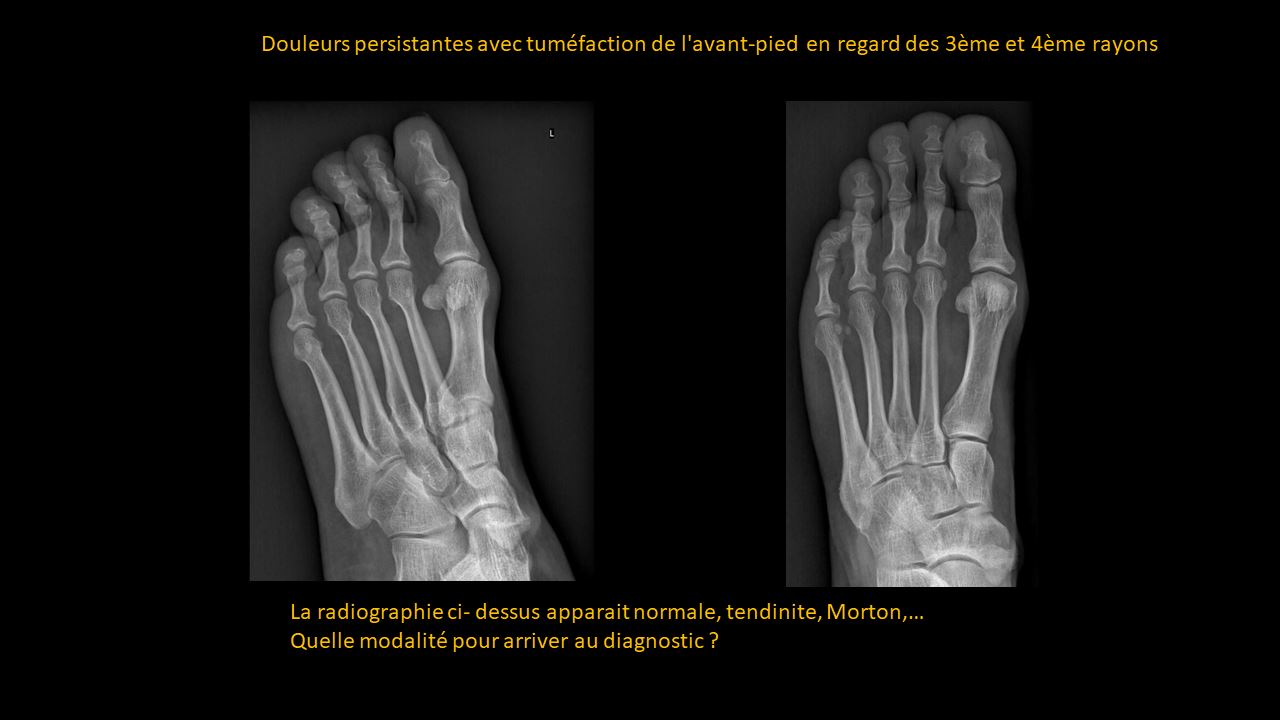

Formation continue sous forme de vignettes ( Quiz )